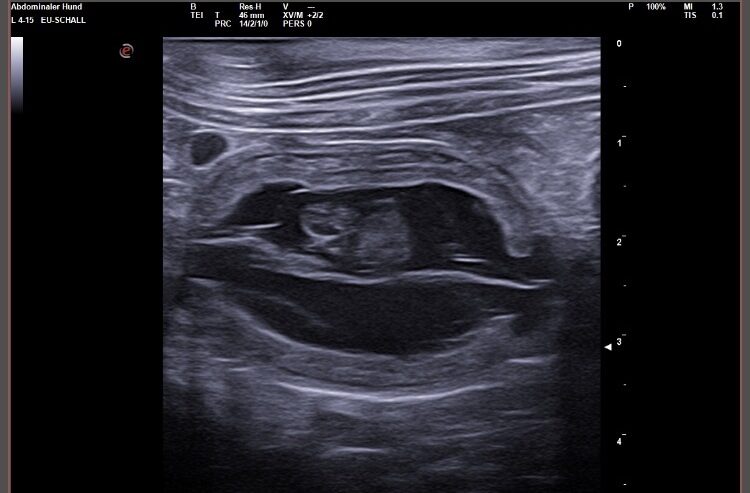

Wir waren erfolgreich und konnten Fruchtanlagen mit schlagenden Herzen sehen. Wir gehen zum aktuellen Zeitpunkt wieder von einem größeren Wurf aus. Daykos und Dorias Rendevouz war also sehr vielversprechend!

Hier zeigen wir euch einige der kleinen gefüllten Fruchtblasen mit Inhalt und schlagenden Herzen. Da wir kurz vor Ostern mit der Geburt rechnen, nennen wir sie „Ostereier“ 🙂